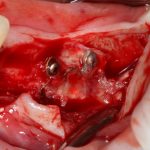

Кстати, обрати внимание на ширину альвеолярного гребня (левая картинка). Она чуть меньше 3 мм. Это объясняет, почему я засомневался в возможности установки имплантатов одновременно с остеопластикой. Понятно и без КЛКТ.

Наперво, мне нужно удалить разрушенный зуб и получить костный аутотрансплантат.

Для получения костного блока, мы открываем донорскую зону, наружную косую линию нижней челюсти.

Возвращаемся к основной операционной области. Еще раз посмотрим на альвеолярный гребень, поофигеваем от его ширины и моих грандиозных планов:

На этом месте мне следует дать некоторые пояснения.

Я зафиксировал костный блок практически без адаптации на несколько винтов. Обрати внимание, что винты находятся в зоне, где не планируется установка имплантатов. Фиксация должна быть надежной, поскольку мне еще предстояла подготовка лунок для имплантатов. Трех винтов для этого вполне достаточно.

Дальнейшая адаптация костного блока свелась к сглаживанию острых краев. После чего я приступил к подготовке лунок и установке имплантатов.